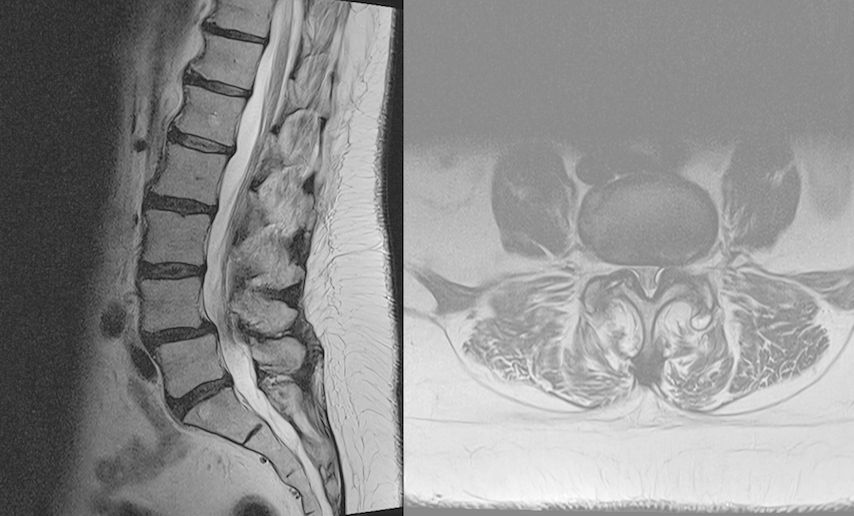

TLIF über Mittellinienzugang mit Schrauben in „cortical bone trajectory“. Bei der 63-jährigen Patientin bestand eine degenerative Spondylolisthese Meyerding Grad I mit Facettengelenkszysten und Wirbelkanalstenose (Abb. 8). Klinisch bestanden Lumboischialgien mit Ausstrahlung dem Dermatom L5 bds. entsprechend. Es wurde ein Mittellinienzugang durchgeführt und zuerst wurden navigierte Schrauben in „cortical bone trajectory“ platziert (Abb. 9). Anschließend erfolgten eine Facettektomie L4/5 links und eine Dekompression des Wirbelkanals. Abbildung 10 zeigt, dass der Hautschnitt aufgrund der mittelliniennahen Schraubenköpfe klein gehalten werden kann. Klinisch wurden die lumbalen Schmerzen wie ausstrahlende Beschwerden 1 Jahr postoperativ annähernd vollständig behoben, die korrespondierende Röntgenkontrolle ist in Abbildung 11 dargestellt.